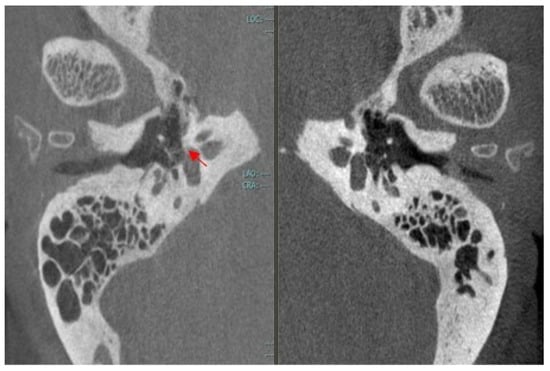

- Outbreak of otosclerosis (3 mm) around the fissula ante fenestram in the right ear (Figure 5).

- Otosclerosis (right ear): Schwartze’s sign, low-frequency conductive hearing loss, type As tympanogram, absent acoustic reflexes, and outbreak of otosclerosis detected by CBCT scan.